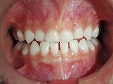

床矯正治療(1期治療)

乳歯の前歯が抜ける6、7歳の時期に上下前歯の歯並びがデコボコしてきた場合は、床矯正(取り外し可能な矯正装置)・食育・咀嚼訓練などを行い口腔周囲筋・咀嚼系筋群を活性させ正常な顎骨に発育させることで歯のデコボコを治していきます。床矯正を始める年齢・永久歯の萠出状態によりワイヤーによる歯列矯正も必要になる場合があります。

受け口(反対咬合)治療は3歳ぐらいから治療可能です。当医院ではパナシールドやムーシールドなどを用いて治療を開始します。

◆床矯正反対咬合

~術前~

~術中~

~術後~